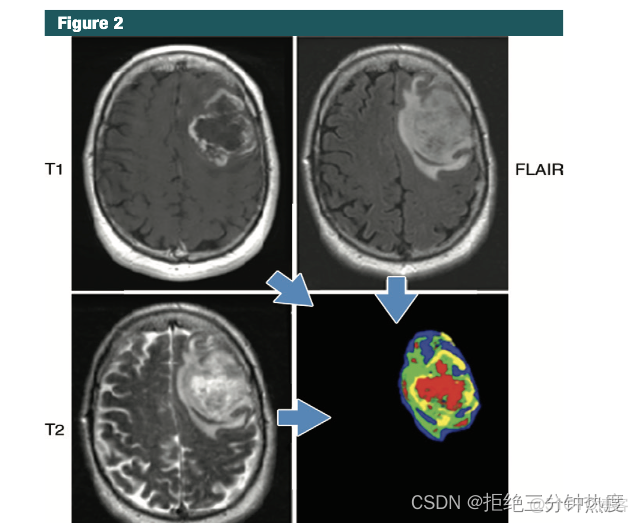

第一方面為輔助鑑別診斷,可以理解為腫瘤(分子)分型,其核心為對(轉移)腫瘤進行分類,以協助臨牀的判斷、提高疾病診斷效率和提供治療方式參考。如乙肝纖維化程度等同病理診斷[2.1];肺結節良惡性鑑別;非小細胞肺癌(NSCLC)分類[2.2];原發、轉移瘤鑑別等;HIV損傷鑑別[2.3];眼眶淋巴瘤和炎性假瘤的無創定量鑑別[2.4];如肝纖維化鑑別以取代肝穿(理論上)。

腦腫瘤[2.12]、鼻咽癌(晚期鼻咽癌無進展生存期精準預測[3.1/3.2])、食管癌[3.3]、肺癌(預測肺癌遠端轉移[3.4])、乳腺癌(組學特徵與乳腺癌復發風險聯繫[發表Nature、新英格蘭、JCO等3.5-3.7]、影像組學評估乳腺癌患者新輔助化療患者的反應[3.8])、結直腸癌[1.2]、膠質瘤、胃腸道癌(胃癌腹膜轉移預測[3.9])、腎癌、膀胱癌、前列腺癌、頭頸部腫瘤、婦科腫瘤、甲狀腺等太多就不一一列舉了。

影像&基因。從生物技術角度看,影像組學是推斷蛋白質基因組和表型信息,因此目前更傾向把他們結合一起分析即放射基因組學(Radigenomics)分析,如影像與基因迴路關聯分析(論文);將影像組學特徵基因組聯合進行miRNA關聯分析[4.2竟然發表了6分+的Cancers!];將腫瘤的水腫/浸潤部分或空間異質性與基因組信息相關聯[4.3,IF=10];MGMT啓動子的甲基化狀態[4.4]、基因突變(影像組學實現結直腸癌KRAS/NRAS/BRAF基因突變精準預測[4.5/4.6/4.7])。